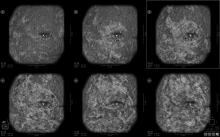

September 20, 2022 — Children and adolescents who have either recovered from COVID-19 or have long COVID show persistent lung damage on MRI, according to a